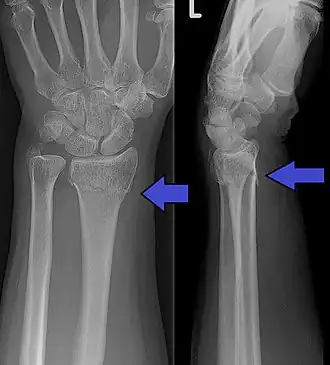

Collesfractuur met ook nog een fractuur van de processus styloides ulnae zichtbaar. | ||||

De term collesfractuur wordt gebruikt voor een extra-articulaire (dat wil zeggen, binnen twee centimeter van maar buiten het polsgewricht gelegen) breuk in het distale eind van het spaakbeen. Hierbij is er per definitie een hoekstand naar achteren, tussen het distale gedeelte (nabij de pols) ten opzichte van het proximale spaakbeen (richting de elleboog).